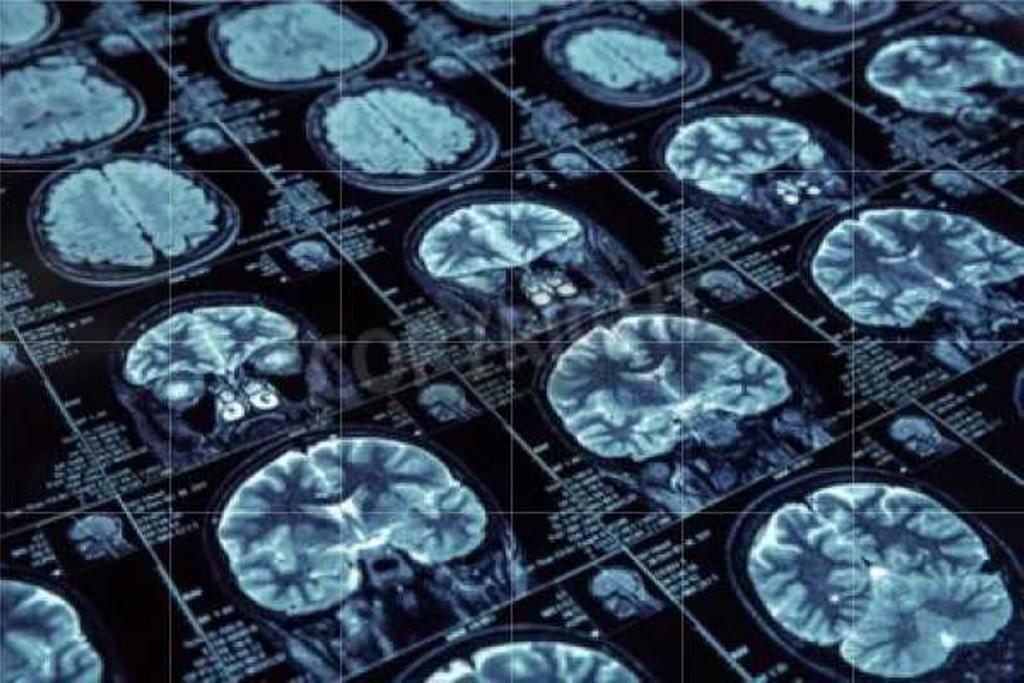

Mediante resonancia magnética funcional, los investigadores compararon la actividad cerebral de personas con TOC y de un grupo sin el trastorno mientras realizaban tareas cotidianas que requerían organización, memoria de trabajo y control mental. Aunque ambos grupos tuvieron un desempeño similar, los participantes con TOC activaron más regiones cerebrales para completar la misma tarea.

Además de los circuitos frontoestriados clásicos, se observaron activaciones en áreas como el giro temporal medio y la unión occipito-temporal, vinculadas al procesamiento del lenguaje, el significado y la percepción visual.